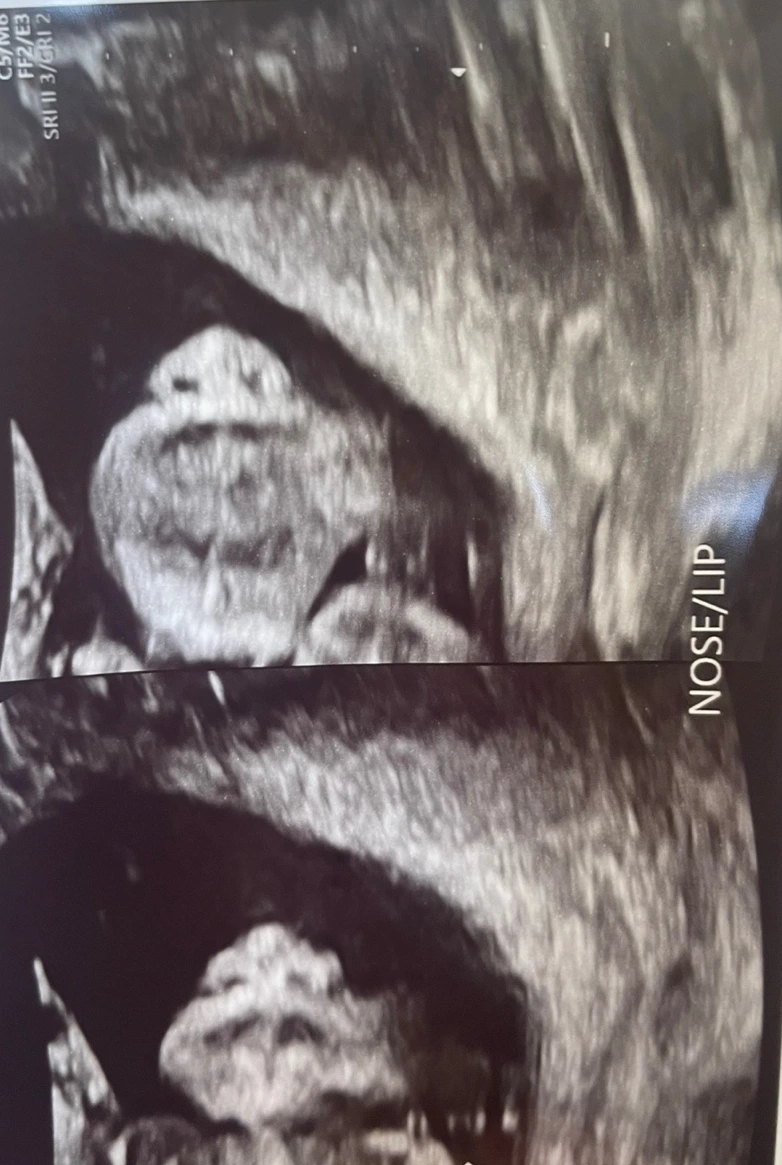

임신 20~22주에 시행하는 정밀 초음파는 아기의 머리부터 발끝까지, 탯줄과 태반까지 아이에게 구조적 이상이 있는지를 확인하는 검사다. 가장 중요한 기관들인 뇌, 심장, 위, 방광 등이 제대로 발달했는지, 사지가 다 붙어 있는지 일일이 확인한다. 손가락 발가락이 10개씩 다 있는지도 이때 확인할 수 있다. 그리고 주요 장기에 혈관들이 잘 연결되어 있는지도 확인하고, 주요 뼈 개수와 태반의 이상 유무, 그리고 구순구개열이 있는지, 귀가 잘 있는지 등을 확인한다.

모든 진료를 끝내고 나서, 수납을 하려고 대기하며 뽑아주신 초음파 사진을 남편과 보는데 구순구개열 확인을 위해 코와 입을 찍은 초음파 사진이 눈에 띄었다. 앙 다문 입과 귀여운 코, 그리고 뽕뽕 보이는 두 개의 콧구멍. 너무 귀엽다. 우리 부부는 집으로 돌아오면서 갑자기 우리 아기는 누구의 코를 닮았을까 확인하기 시작했다. 첫째 딸은 아빠 닮는 게 국룰이라는데, 역시나 코가 아빠를 닮았다. 거울을 보며 '음~ 내 코 모양이랑은 달라'라고 체념하고는, 남편에게 고개를 들어보라고 하며 코를 봤는데, 빵 터졌다. 어쩜 이렇게 모양이 똑같을 수 있지? 생각해보면, 내 주변 장녀들은 다 아빠를 닮았다고 했다. 물론 나도 그러하다. 어렸을 때 우리 아빠를 처음 보는 사람도 '어머~ 뿅뿅이 아버님이시죠'라고 바로 물어보곤 했다고.

아빠를 쏙 빼닮은 코. 너무 귀여워...